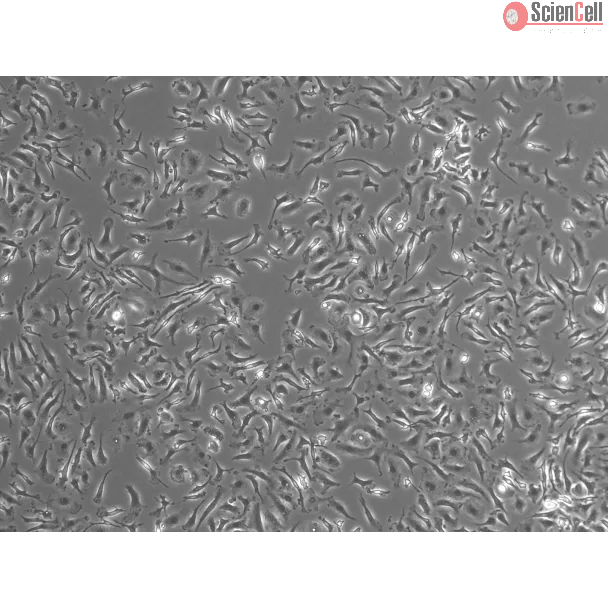

Mouse Pulmonary Alveolar Macrophages

Pulmonary alveolar macrophages (PAMa) are located in the alveoli of the lungs and protect the respiratory tract against respiratory pathogens. PAMa are the main phagocytes of the innate immune system and they originate from the yolk sac. Functionally, PAMa are tasked with maintaining pulmonary homeostasis and protecting the body from invading pathogens.